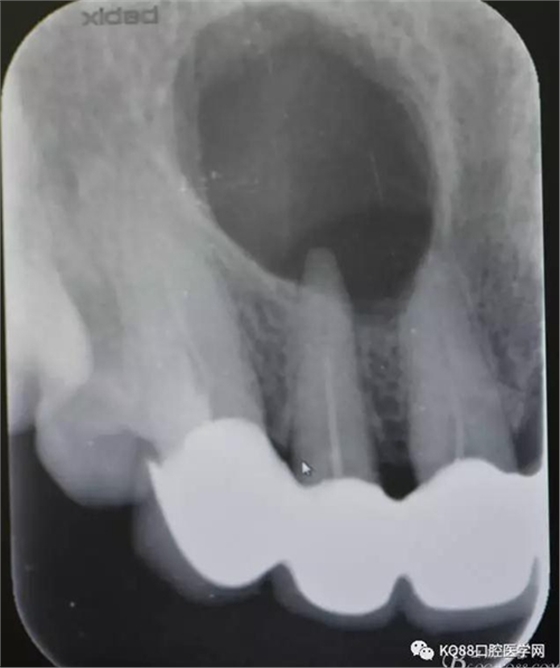

圖1.術(shù)前的根尖片影像檢查:11、12根管治療不完善